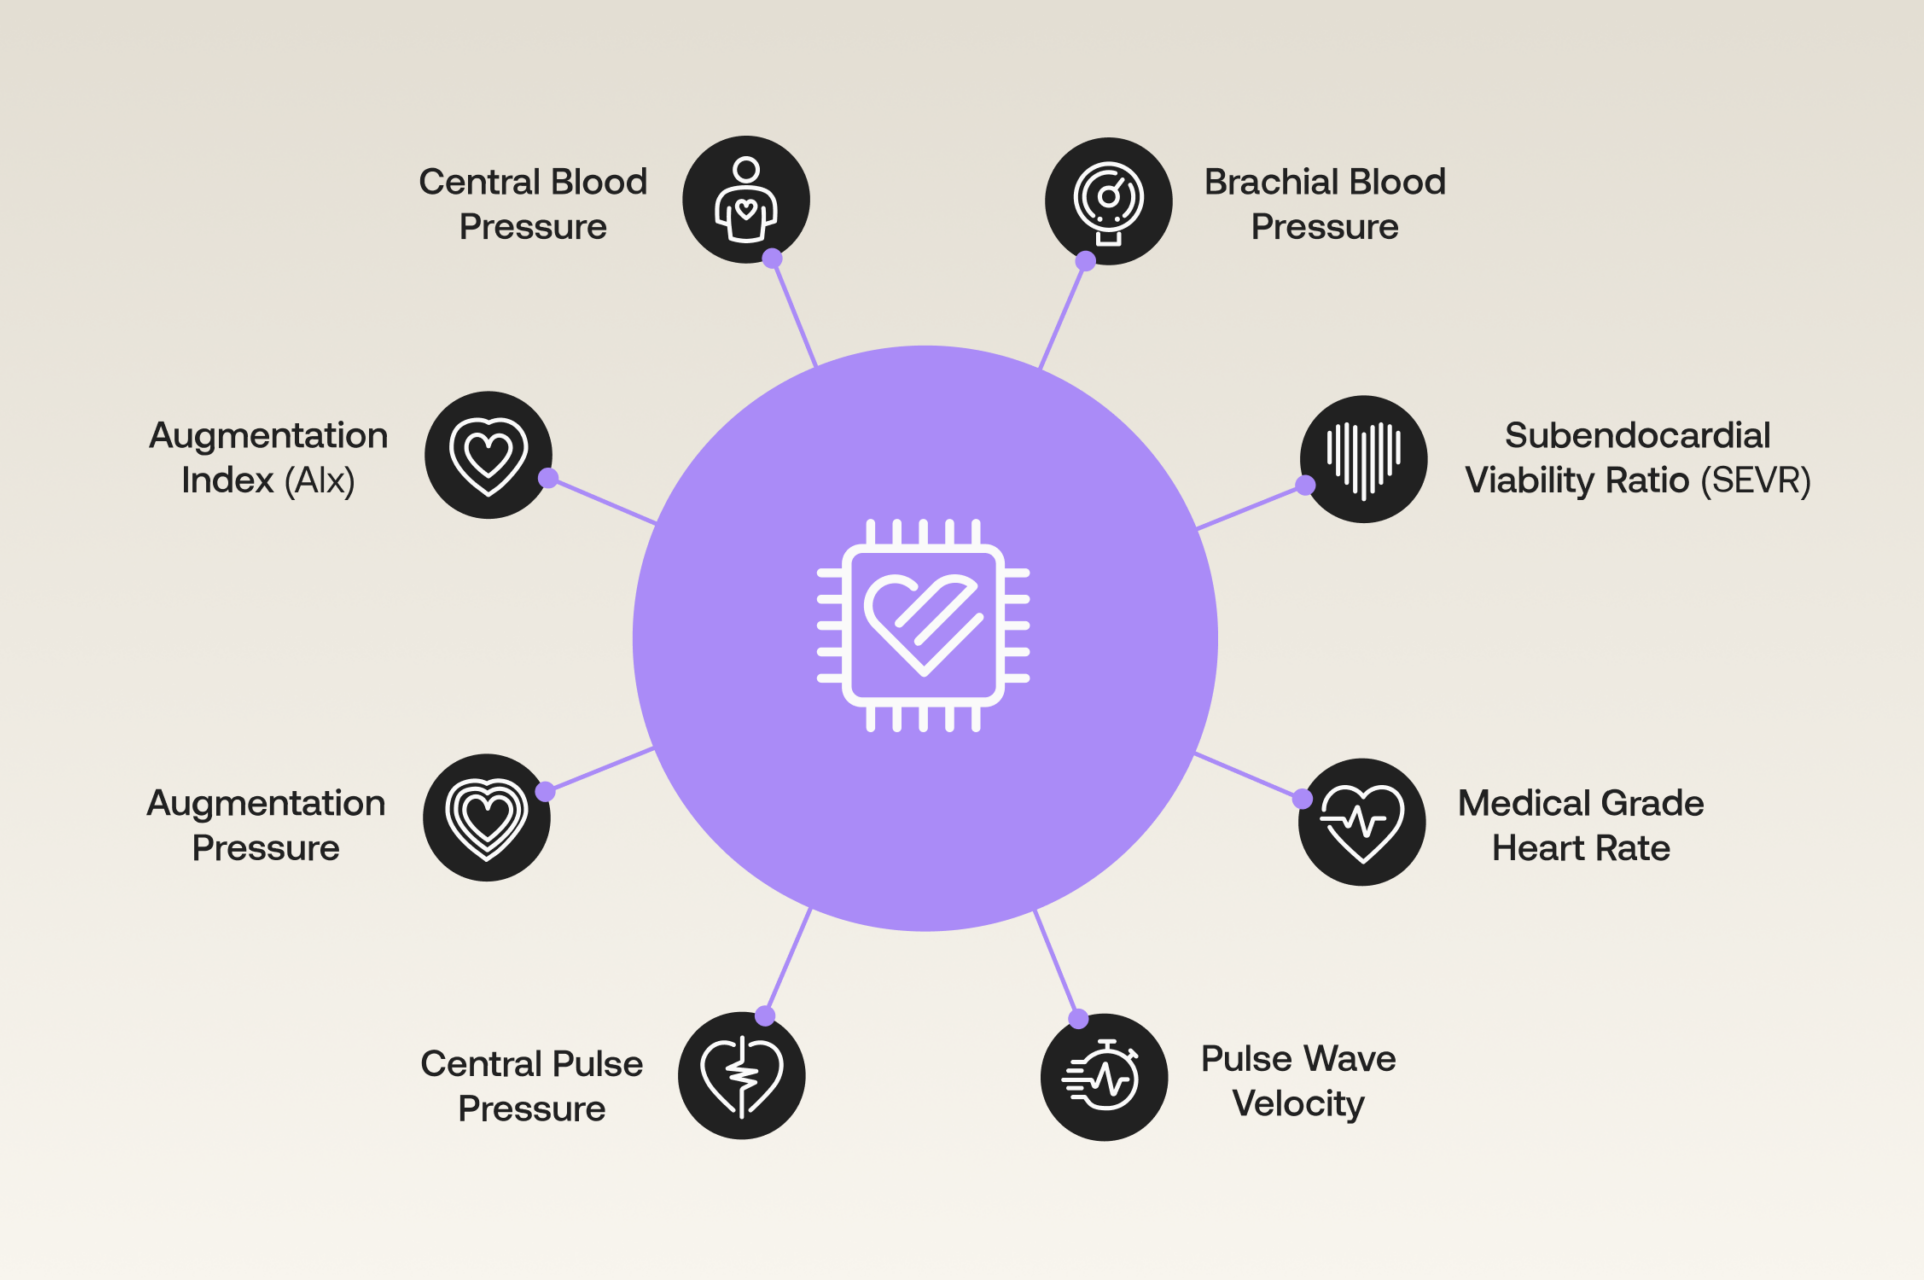

Join us to learn the fundamentals of vascular system, central blood pressure and vascular health monitoring. Learn the essentials, explore tools, and understand the importance of monitoring arterial health.

This course delves into the mechanisms and tools for assessing central hemodynamics, covering invasive and noninvasive methods, patient monitoring, medical device regulation, and cuffless blood pressure monitoring.

Deepen your diagnostic toolkit by mastering Pulse Wave Analysis. Uncover arterial stiffness, central pressures, and early risk signals that sharpen treatment decisions and improve patient outcomes.

Join our mini masterclass on Pulse Wave Analysis (PWA) and Pulse Wave Velocity (PWV)—and explore how these powerful tools reveal insights into arterial stiffness, cardiovascular risk, and patient outcomes.